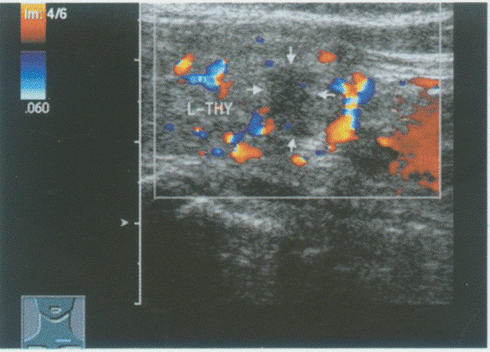

176、单项选择题

临床资料:女性,25岁,自述心悸,多汗,食欲亢进,体重减轻6个月余,发现颈部增粗1周。临床物理检查:甲状腺对称性增大,随吞咽上下运动,听诊有血管杂音。超声综合描述:双侧甲状腺增大,回声减低,明显不均,内未见囊实性肿物,CDFI:内可见丰富动静脉血流信号,呈"火海"征。见下图及彩图。

超声提示()。

A.结节性甲状腺肿

B.毒性甲状腺肿(原发性甲状腺功能亢进)

C.甲状腺腺瘤

D.甲状腺正常声像图

177、单项选择题